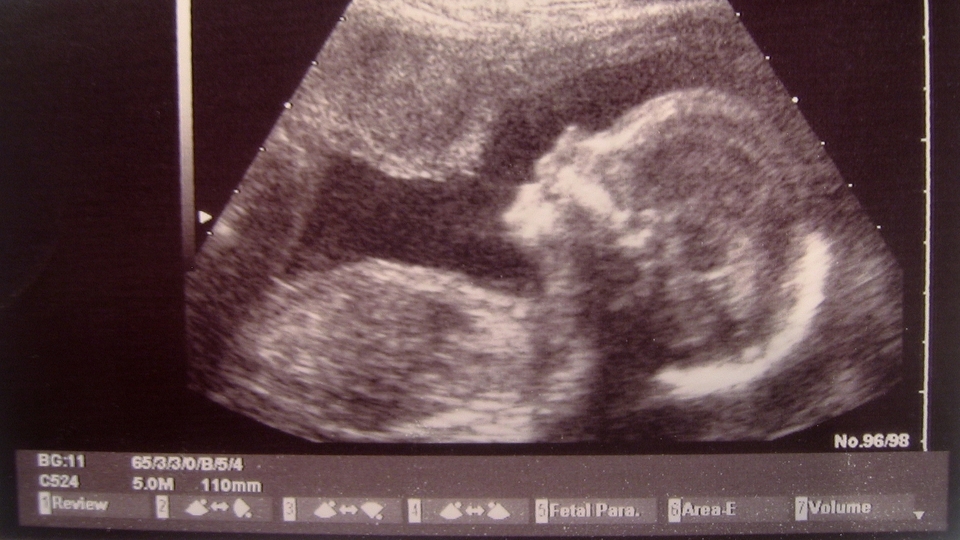

ABD'nin Teksas eyaletinde yaşayan bir çift, hamilelik döneminde aynı bebeği birlikte bedenlerinde taşıdılar. Eşcinsel çift, aynı bebeği bedenlerinde taşıyarak, tıp tarihine geçtiler.

New York Post'ta yer alan habere göre; Haziran 2015'te evlenen Ashleigh ve Bliss Coulter çifti, bebek sahibi olabilmek için çok sayıda doktora gitti. Doktorlardan bir tanesi birlikte bebek sahibi olabileceklerine dair umut verdi. Biyolojik olarak yalnızca bir anne hamileliği yaşayabiliyorken, yapılan bir uygulamayla hem Ashleigh hem de Bliss bebeklerini bedenlerinde taşıdılar.

İki Taraflı Zahmetsiz Tüp Bebek (ER-IVF) adı verilen deneysel yöntemle her ikisi de döllenme sonrası oğullarını fiziksel olarak bedenlerinde taşıdı.

Bir donörden sperm alındı. Bliss'in döllenen yumurtası, kuluçka makinesi yerine Bliss'in rahminde ilk oluşum sürecini tamamladı. Beş gün sonra da bebek hormon terapisi alan Ashleigh'e nakledildi.

Stetson adı verdikleri oğulları, herhangi bir sorun yaşanmadan dünyaya gözlerini açtı.